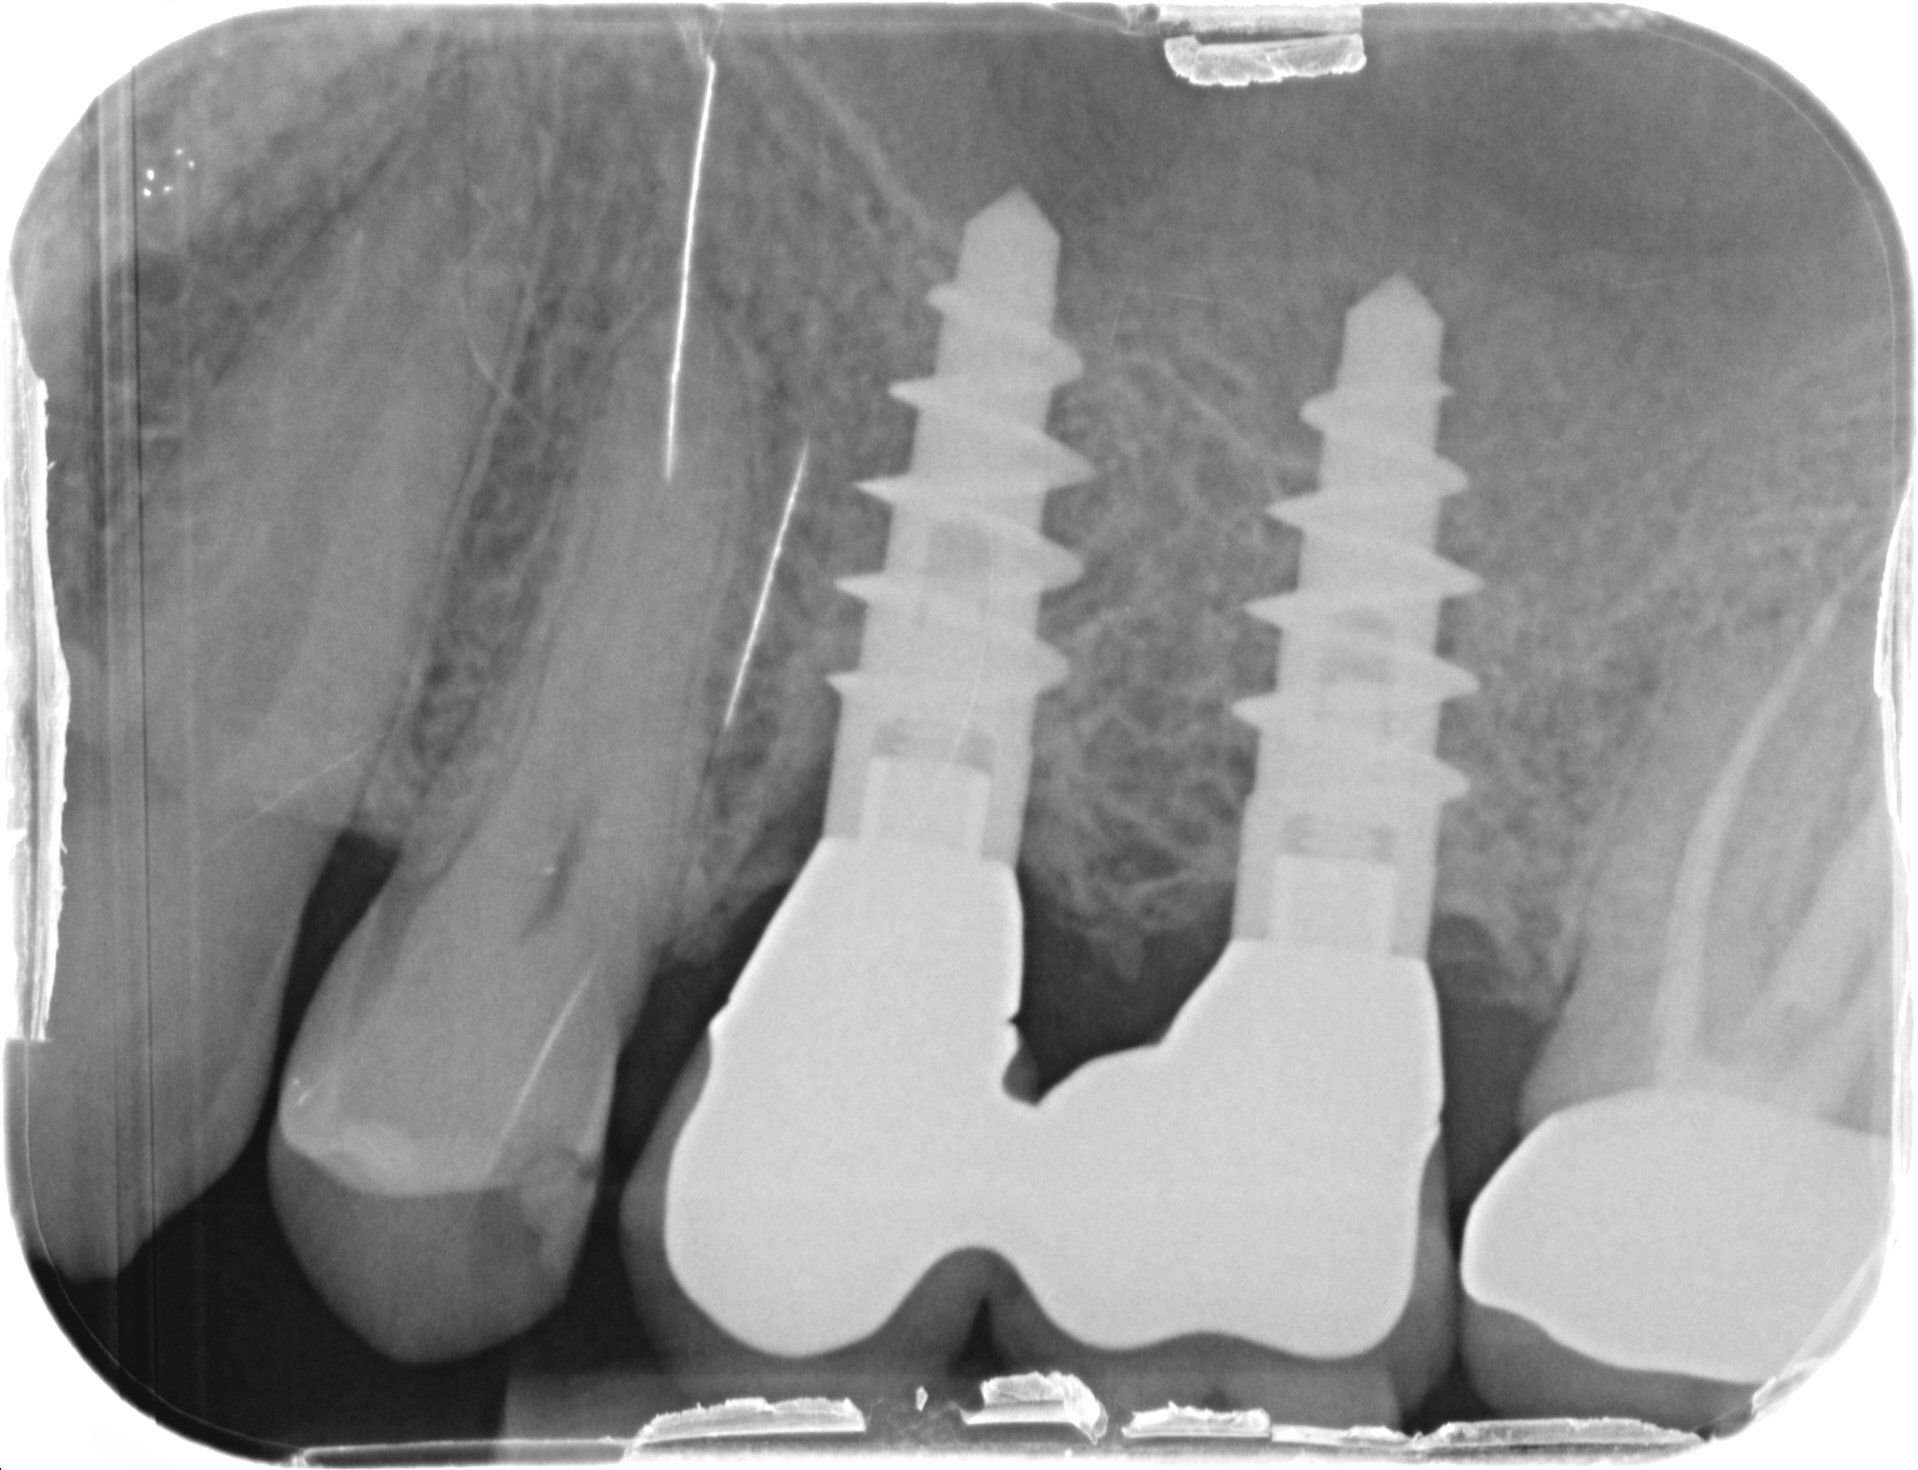

Dopo novanta giorni (T3) si evidenzia una situazione di stabilità (Fig. 14, 15 e 16). Il P.I. corrisponde all’ 8% e il BoP all’1% (Fig. 17).

#dida Fig.16: Radiografia endorale a T3